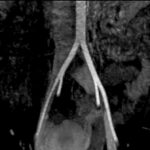

Fig. 8 y Fig. 9. AngioRM demostrando la dilatación de la VICI luego del pasaje entre AICD y la columna.

Se corrobora el diagnóstico presuntivo con flebografía y angioresonancia, observándose compresión de la VICI entre la columna y AICD y su dilatación distal (Fig. 8 y Fig. 9).